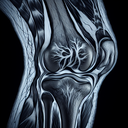

МРТ колінного суглобу

МРТ (магнітно-резонансна томографія) колінного суглоба – це неінвазивний діагностичний метод, який дозволяє отримати чіткі зображення внутрішніх структур коліна. Це дослідження особливо корисне для оцінки стану м'яких тканин, таких як зв'язки, сухожилля, хрящі та меніски. ### Навіщо роблять МРТ коліна...